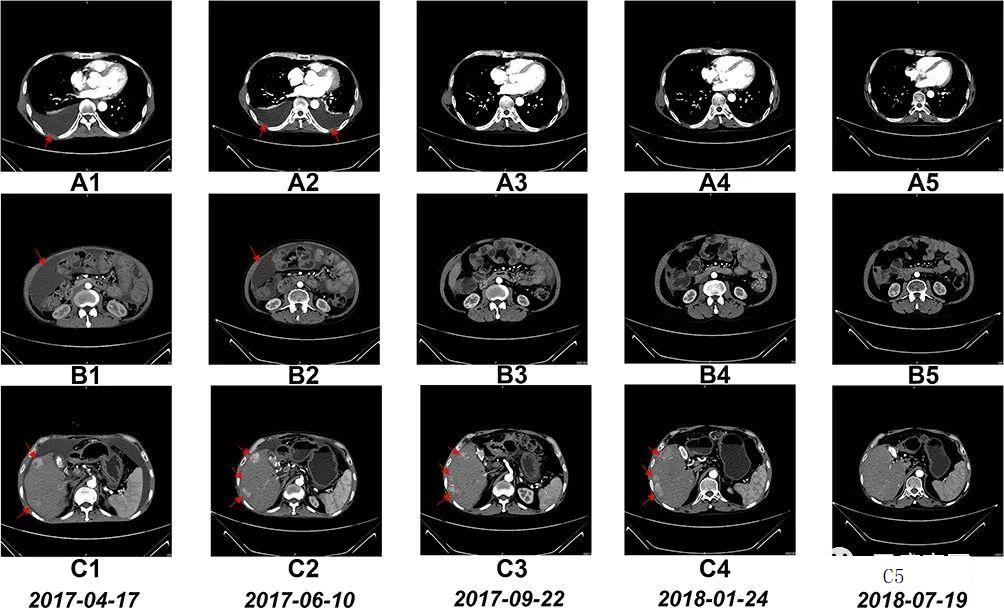

NK细胞治疗前和治疗期间的CT扫描结果

图A1~A5:CT扫描显示,6个疗程后胸腔积液完全消失;

图B1~B5:CT扫描显示,6个疗程后腹水几乎完全消失;

图C1~C5:CT:扫描显示,肝右叶多个肿瘤的大小在17 个疗程后显著缩小;